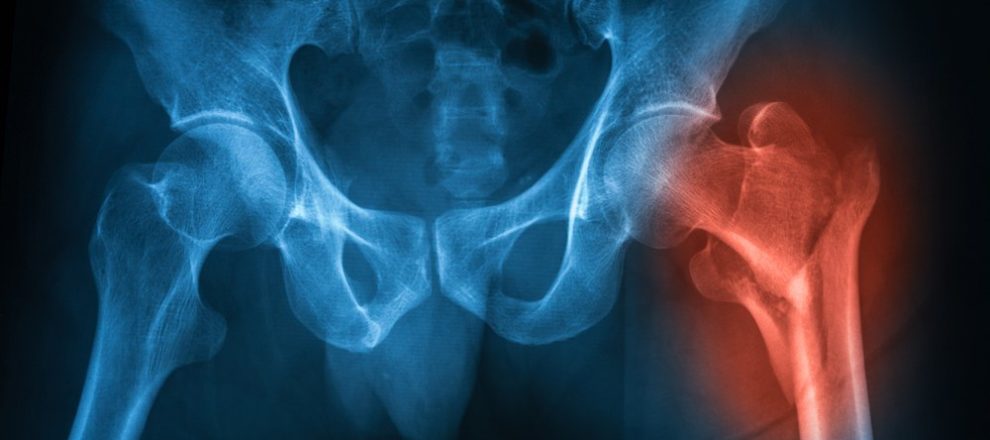

ROMA – 22 APR – “Nel Lazio gli interventi chirurgici entro i due giorni per la frattura del femore sono quasi raddoppiati passando dal 31% (2012) al 57,5% (2018). Un dato molto significativo che rappresenta il miglioramento della qualita’ delle cure nella nostra Regione”: lo ha annunciato l’assessore alla Sanita’ e l’Integrazione sociosanitaria della Regione Lazio, Alessio D’Amato.

“Sappiamo quanto nel caso specifico della frattura del femore, soprattutto in soggetti in eta’ avanzata, operare con tempestivita’ ed entro le 48 ore- conclude D’Amato- non solo sia un fattore di qualita’ di assistenza, ma salvi la vita del paziente. Un intervento tardivo infatti aumenta notevolmente il tasso di mortalita’. Il Lazio oggi ha un sistema sanitario che migliora di anno in anno nell’erogazione dei Livelli essenziali di assistenza (LEA) con risultati molto soddisfacenti soprattutto sulla prevenzione ed in particolare sulle coperture vaccinali nei bambini che vede il Lazio come leader nazionale. Inoltre migliora il tasso di ospedalizzazione, l’appropriatezza dei ricoveri e aumenta sensibilmente la percentuale degli anziani trattati in assistenza domiciliare”.